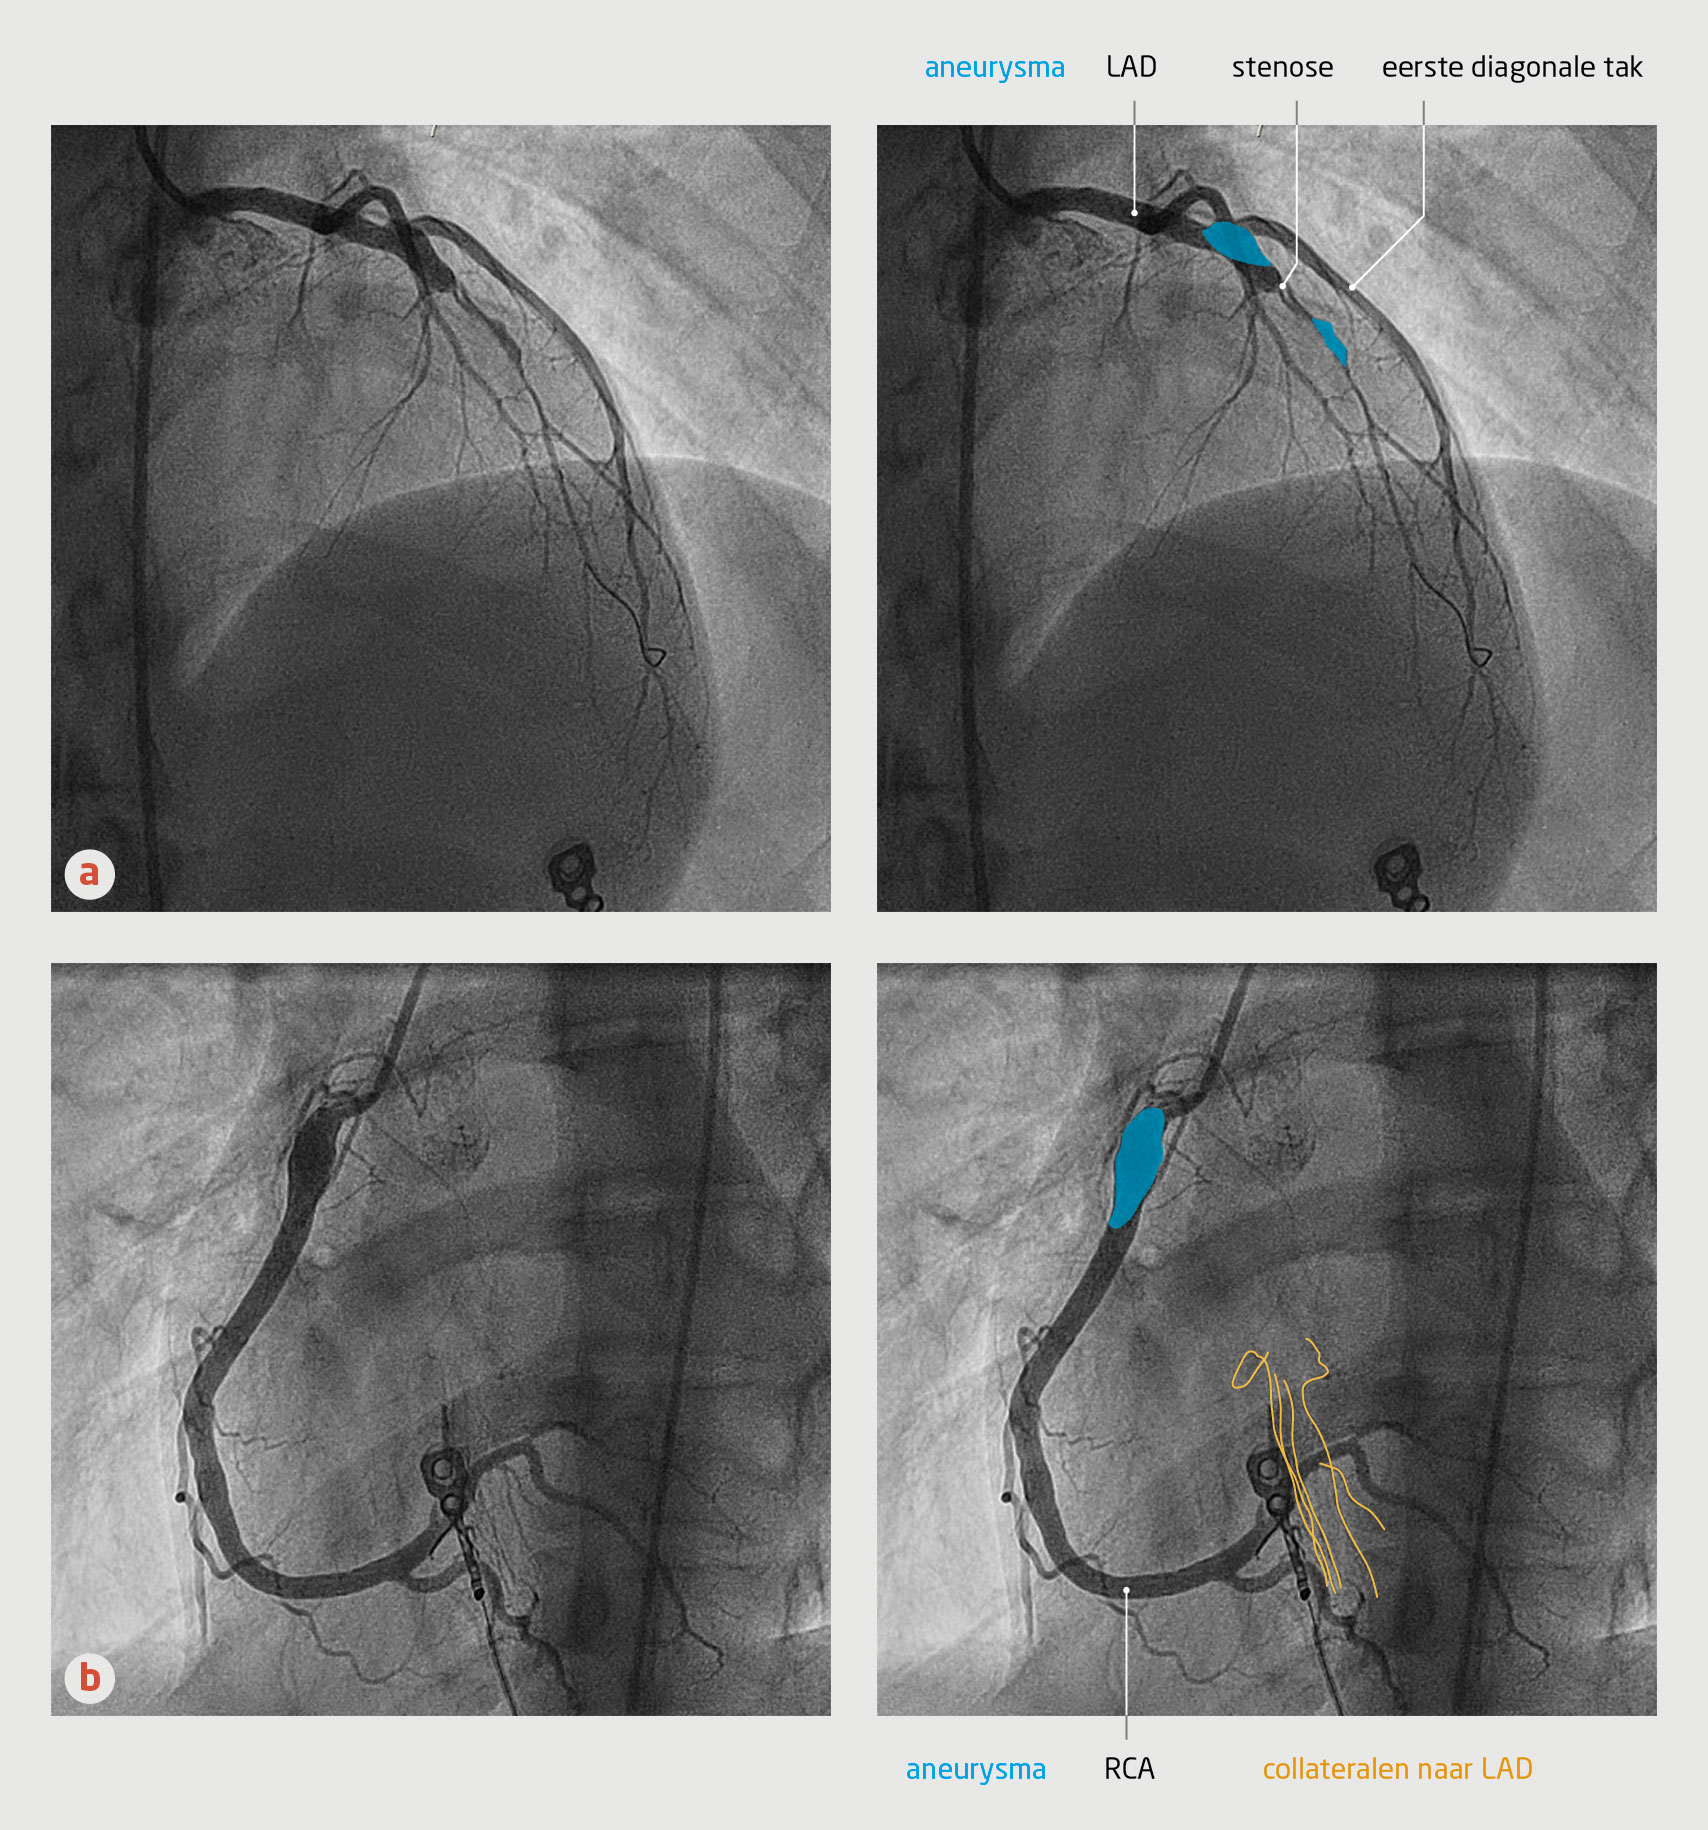

Bij de hartkatheterisatie bleken alle coronairvaten aneurysmatisch gedilateerd te zijn. In de proximale ‘left anterior descending artery’ (LAD, ramus descendens anterior) was een aneurysma zichtbaar met distaal hierin een trombotische occlusie (figuur 1a). Ook werden uitgebreide collateralen gezien die pasten bij reeds langer bestaande stenoses (figuur 1b). Van deze beelden zijn video’s beschikbaar. Wij verrichtten een percutane coronaire interventie van de LAD waarbij een drug-eluting stent werd geplaatst. Daarna werd de patiënt opgenomen op de IC voor temperatuurregulatie. De uitslag van de toxicologische screening van urine op onder andere cocaïne bleek negatief. Na 24 uur opname op de IC volgde overplaatsing naar de hartbewaking.

Figuur 1 | Linker en rechter coronairarterie van een 18-jarige man met een acuut myocardinfarct

Angiografische beelden van de coronairvaten van een 18-jarige man die gereanimeerd was na een acuut myocardinfarct, (a) linker coronairarterie en (b) rechter coronairarterie. De LAD vertoont aneurysma’s en een stenose, de RCA een aneurysma en collaterale verbindingen met het stroomgebied van de linker coronairarterie. De aneurysma’s zijn een gevolg van de ziekte van Kawasaki die deze patiënt 4 jaar eerder had doorgemaakt. LAD = ramus descendens anterior; RCA = rechter coronairarterie.

Angiografie van de linker coronairarterie bij een 18-jarige man die kort daarvoor een acuut myocardinfarct had doorgemaakt. Er zijn aneurysmata en een stenose zichtbaar.

Angiografie van de rechter coronairarterie bij een 18-jarige man die kort daarvoor een acuut myocardinfarct had doorgemaakt. Er is een aneurysma zichtbaar en er worden collateralen aangekleurd die verbinding hebben met het stroomgebied van de linker coronairarterie.